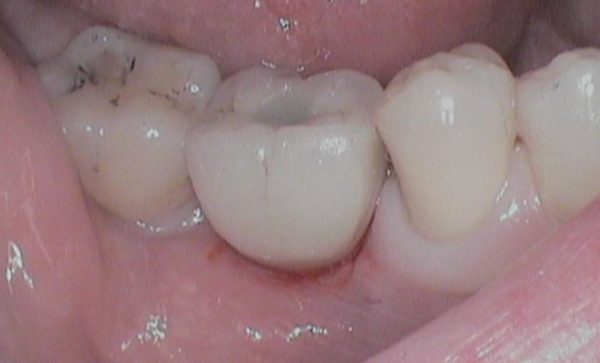

Case 32